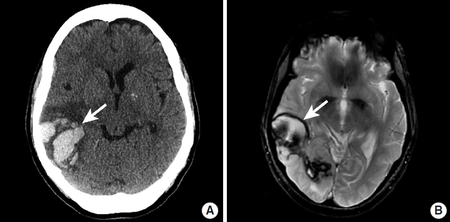

뇌색전증 진행 과정의 후속으로 출혈을 일으키기 쉬운 것도 하나의 특징으로 MRI 검사로 확인할 수 있습니다. 혈전이 초기 위치에서 말초 쪽으로 이동하면 경색 내의 혈관으로 다시 관류되어 출혈이 생기기 쉽습니다. 반면 혈전성 뇌경색으로는 병소가 이동하지 않기 때문에 이러한 후속 출혈은 나타나지 않습니다.뇌색전증에서는 색전의 원인이 될 수 있는 심장 질환을 심전도나 심장 초음파로 찾아내는 것도 필요합니다.